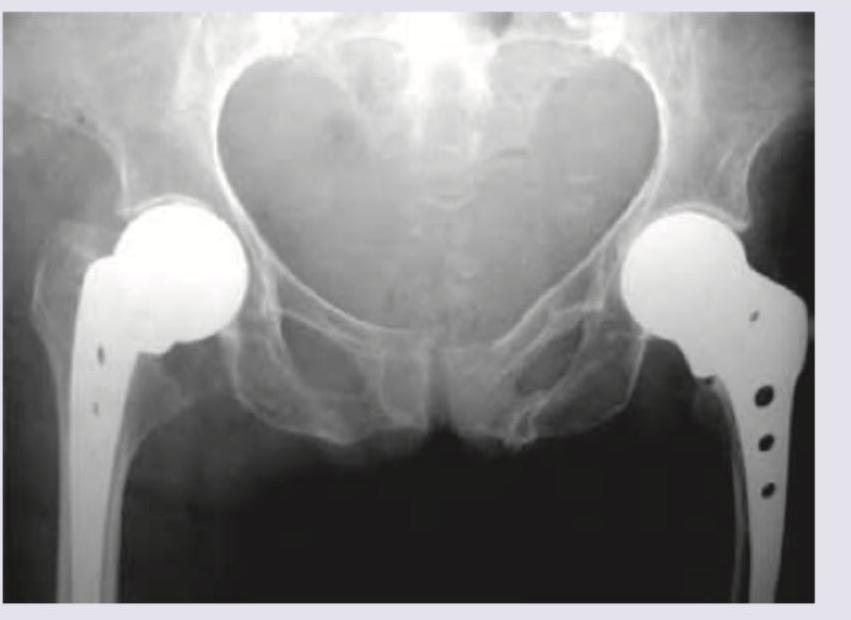

Which prosthesis is shown below in the X-ray?

Explanation: ***Austin Moore's prosthesis*** - The image clearly shows a unipolar femoral head prosthesis with a **fenestrated stem** for bony ingrowth, which is characteristic of the Austin Moore design. - This prosthesis is typically used in **hemiarthroplasty** for femoral neck fractures or avascular necrosis, where the acetabulum is preserved. *Thompson prosthesis* - While also a unipolar hemiarthroplasty, the Thompson prosthesis has a **collar** and a **solid stem** without fenestrations, which differentiates it from the one pictured. - It is also primarily used in hip hemiarthroplasty. *Articular resurfacing* - Articular resurfacing involves capping both the femoral head and the acetabulum with metallic implants, preserving more bone than traditional hip replacement. - The X-ray shows a stem extending into the femoral shaft, which is not consistent with **acetabular resurfacing**. *Birmingham hip* - The Birmingham hip is a type of **hip resurfacing arthroplasty**, characterized by a metal cap on the femoral head and a metal cup in the acetabulum. - The prosthesis shown has a **femoral stem**, thus it is not a resurfacing implant like the Birmingham hip.